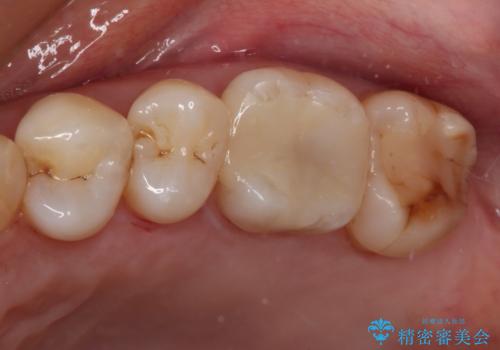

インプラントの埋入は矯正治療中に行い、矯正治療後はインプラント上補綴および、前歯のセラミック治療を行いました。

インビザラインによる治療を希望されたため、左側のスペースは閉じ、右側はスペースをより拡大し、インプラント補綴を行うこととしました。